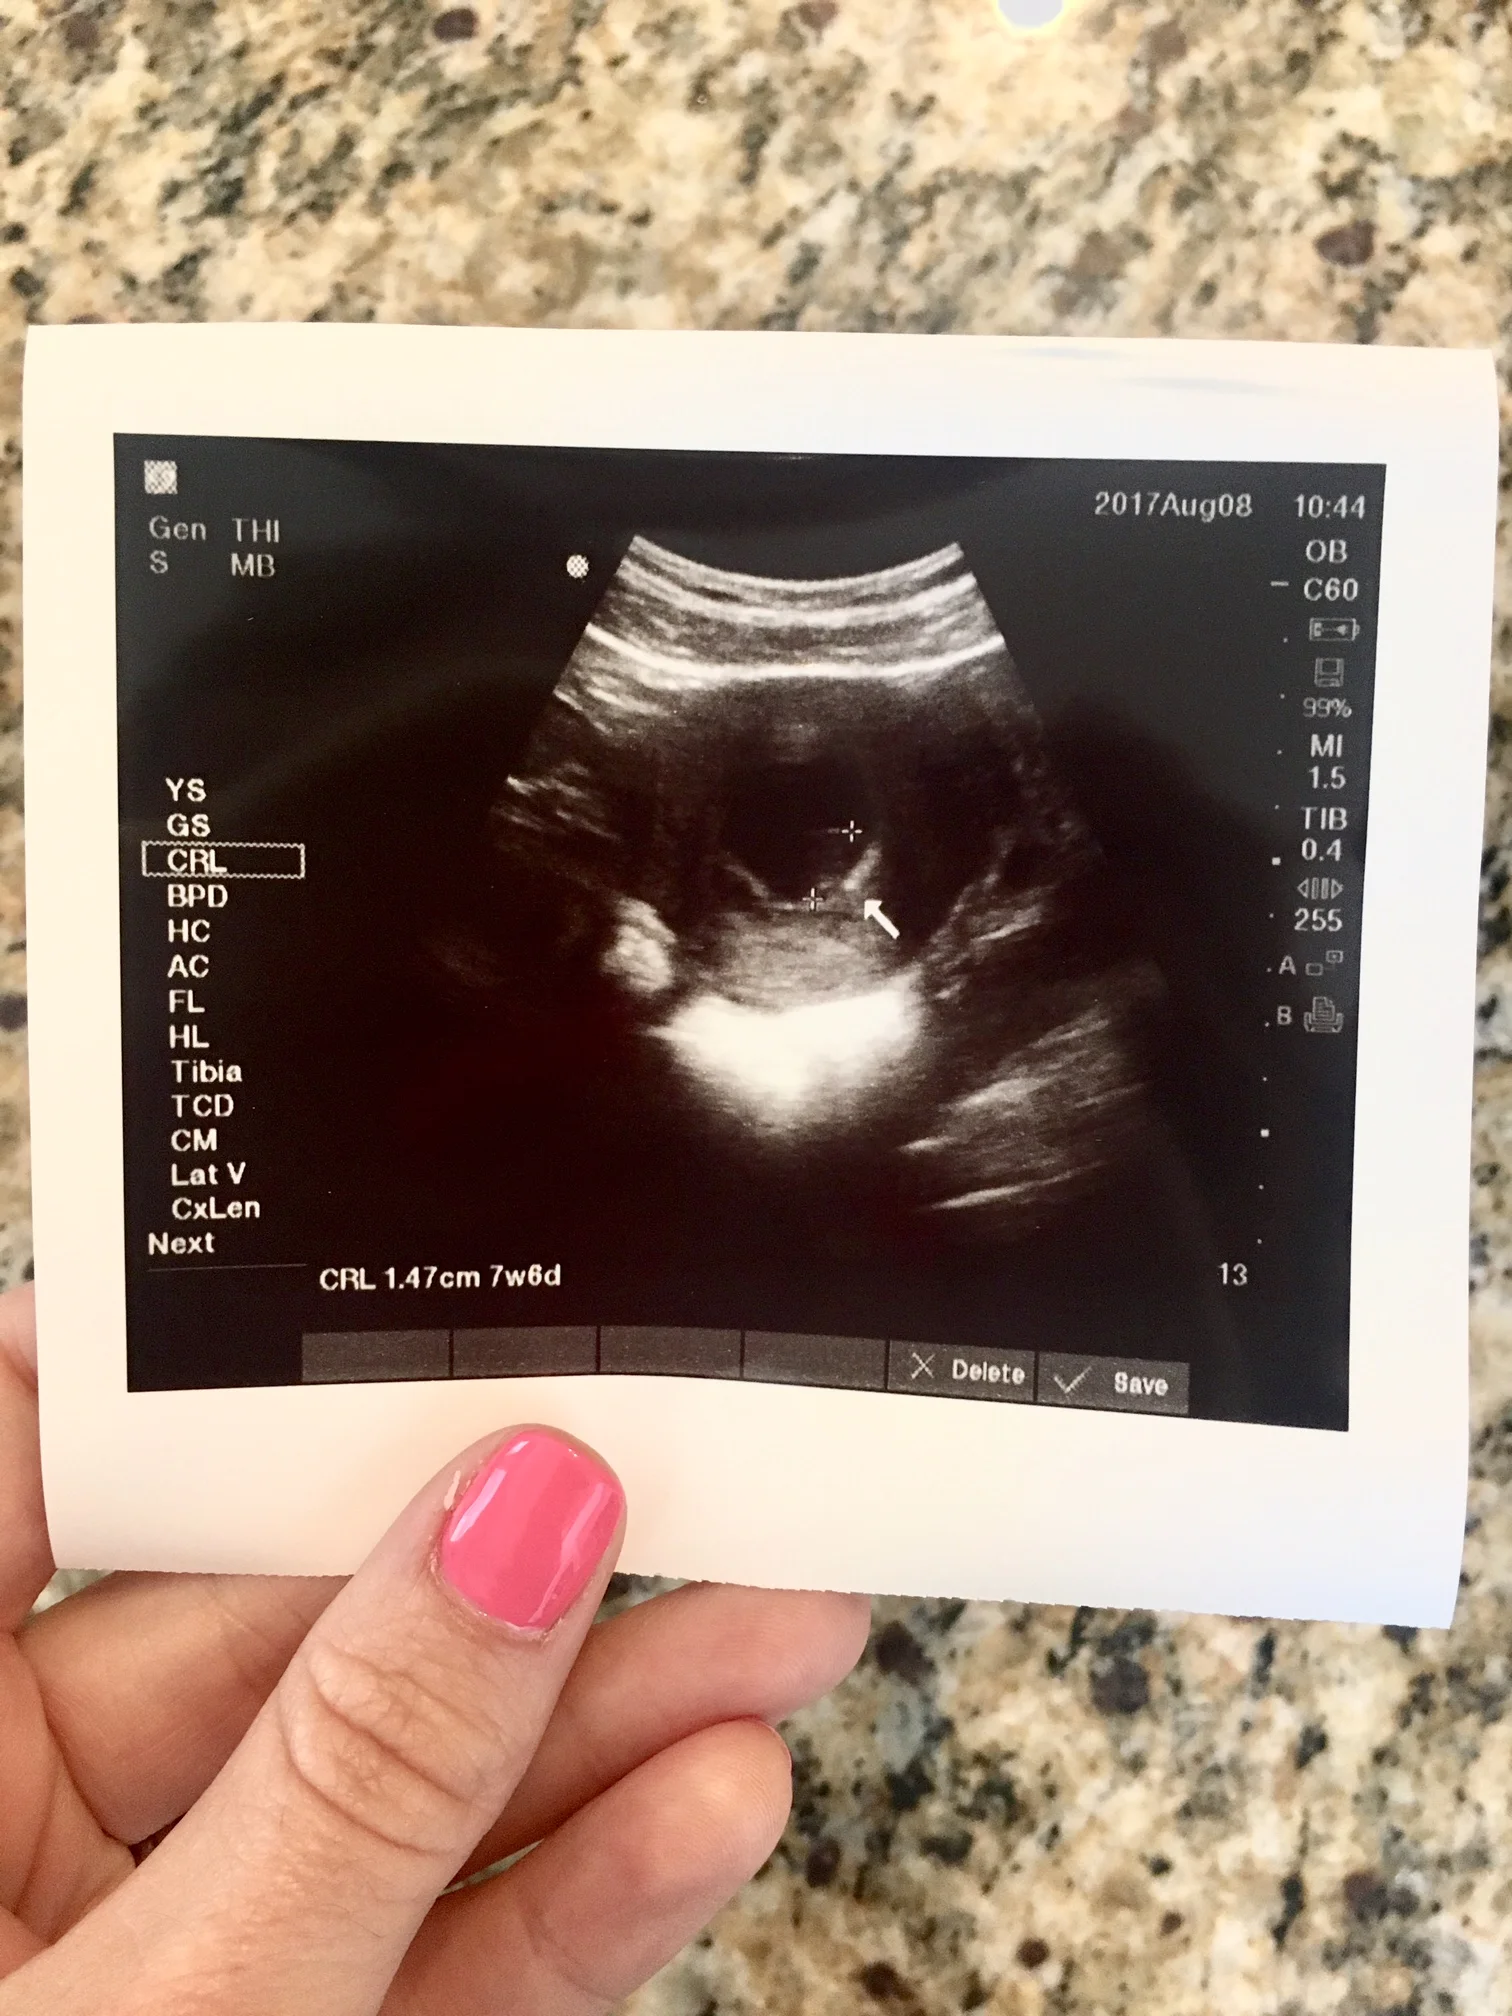

We were supposed to have our (almost) 8 week ultrasound the very next day - a day we were SO excited about. We were going to see our baby for the first time! I called my doctor and they moved my appointment up so they could see me that afternoon. Kevin came home from work early and we headed to the doctor's office filled with excitement, a little bit of concern, but mostly excitement. I hadn't had any other trouble leading up to this day, so it just had to be a fluke thing, right?

She pulled out the ultrasound machine, squeezed that cold blue gel on my belly that I'd always wondered what would feel like, and started rolling the wand around. I had one hand behind my head, the other in Kevin's, and I just kept looking back and forth between the screen and the nurse, hoping she'd tell me what she was seeing. She wasn't saying anything.

"Oh my gosh, why isn't she saying anything!" I thought. I pinched my fingers together to try to distract my tears, and stared at that screen so hard to try to figure out what I was looking at. It was my first ultrasound, after all, and I didn't really know what the different shapes were quite yet.

She took the wand off me, turned to look at us and said, "I don't see a heartbeat."

"Yes there is a baby. I'd like to try one more way to try to see the heartbeat, just to be sure," she said. So she tried again.

And again she said, "I don't see a heartbeat."

Our babe the size of a blueberry.